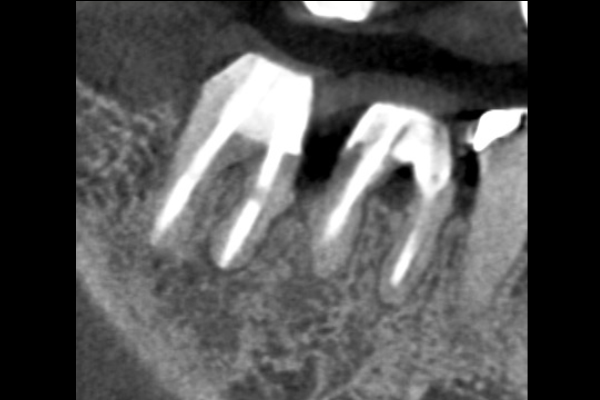

【札幌駅前】精密根管治療

30代男性の小臼歯(奥歯)の症例

- 主訴

- 「奥歯で咬むと違和感がある」「時々歯茎が腫れる」とのことでご来院されました。数週間前から症状があり、他の医院では「抜歯の可能性がある」と言われ、不安に感じていらっしゃいました。

- 期間

- 治療期間2ヶ月、治療回数3回、レントゲン写真で治癒を確認できるまでの期間6ヶ月

- 治療内容

- 1.古い被せ物の除去と虫歯の徹底除去

まず、古い銀歯を外し、内部に広がっていた虫歯を丁寧に取り除きました。

2.マイクロスコープ下での根管治療

唾液などによる細菌の侵入を防ぐ「ラバーダム」を装着し、マイクロスコープ(歯科用顕微鏡)で根管内を数十倍に拡大しながら治療を進めました。複雑な形状の根管の内部まで、汚染された組織を徹底的に洗浄・消毒します。

3.根管充填(こんかんじゅうてん)

根管内が完全にクリーンになったことを確認し、再感染を防ぐために専用の薬剤で隙間なく密閉しました。

4.土台と被せ物の作製

歯の強度を補うための土台を立て、最終的なセラミックの被せ物を作製し、装着しました。